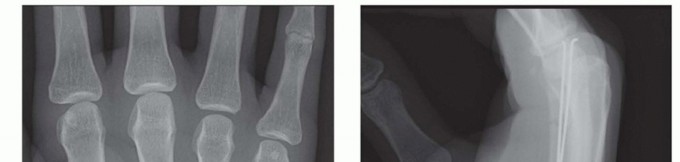

Standard radiographic imaging forms the cornerstone of diagnostic evaluation, requiring, at minimum, a dedicated posteroanterior (PA), a true lateral, and a pronated oblique view of the injured hand. The PA view is excellent for assessing coronal plane angulation and transverse displacement, though it notoriously underestimates sagittal plane deformity. The true lateral view is critical for quantifying apex-dorsal angulation, though overlapping metacarpal shadows can complicate interpretation. The pronated oblique view often provides the clearest visualization of the fracture profile and the degree of comminution.

When standard radiographs are equivocal, or when dealing with complex intra-articular fractures and suspected CMC fracture-dislocations, advanced cross-sectional imaging is mandatory. High-resolution Computed Tomography (CT) with 3D reconstructions provides unparalleled detail of articular step-offs, occult comminution, and the precise spatial orientation of fracture fragments. This information is invaluable for determining the feasibility of lag screw fixation versus the necessity of bridge plating. Furthermore, obtaining radiographs of the uninjured, contralateral hand serves as a vital anatomical template, allowing the surgeon to accurately gauge the patient's native metacarpal length and intrinsic diaphyseal curvature.

Clinical & Radiographic Imaging Archive